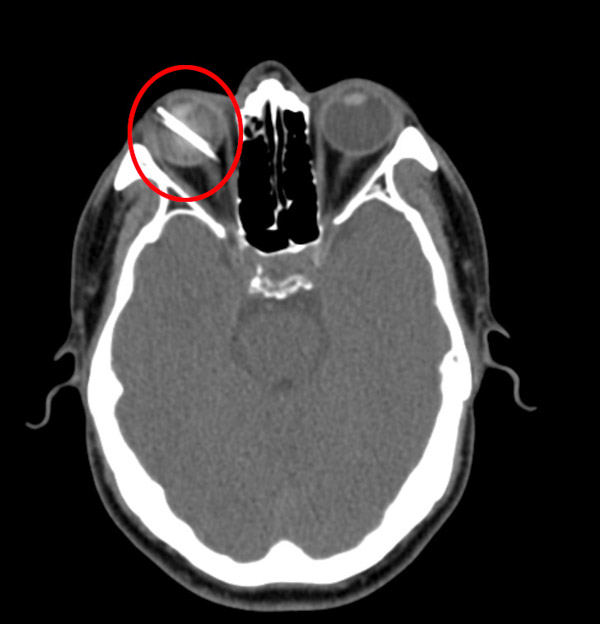

我院眼科中心付鵬醫生仔細檢查了患者的病情,初步診斷為右眼眼球貫通傷伴異物嵌頓。“不幸中的萬幸,這顆釘子雖然從眼球壁上打穿了眼球和視網膜,但沒有傷到角膜和晶體,也沒有扎到大的血管和視神經。”付鵬讓患者放心,表示一定盡全力挽救他的眼睛與視力。聽到付鵬醫生這樣說,患者一顆惴惴不安的心放了下來。

隨后,眼科中心團隊制定了詳細的治療方案,對患者進行手術治療,通過后入玻璃體切割術+后段眼球壁異物取出術+玻璃體硅油填充術,將長約2.5cm的鐵釘從患者右眼中取出,并填充硅油,保持眼壓,經過一個多小時,手術順利完成,成功挽救了患者右眼視力。